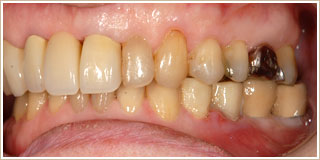

ケース1

噛みにくい。

腰や背中、肩、首の痛みを軽減したい。

口元を美しくしたい。

▼治療前

むし歯や歯周病の治療を行います。

歯の抜けた所にはインプラント(矢印部分)を埋入します。

下顎には歯列矯正を行いました。 歯列矯正の期間は、3ヶ月でした。

クラウンをかぶせるために、歯の形を整えます。

そして、歯型を採って模型上でセラミッククラウンを製作します。

1ヶ月に約8回の受診で、全治療期間は12ヶ月でした。